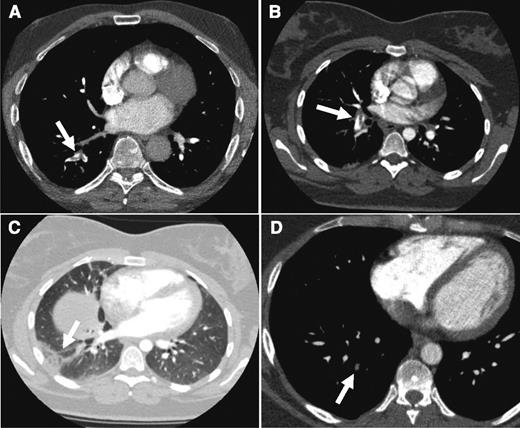

As for our patient, both the Wells rule and the revised Geneva score indicated an unlikely probability (Wells score: 3 points for PE as the most likely diagnosis; revised Geneva score: 1 point for age >65 years). Subsequent laboratory testing revealed an elevated d-dimer level of 2200 µg/L. Even when an age-dependent cutoff was applied (age 69, adjusted d-dimer cutoff 69 × 10 = 690 µg/L), this concentration was well above the normal threshold. Consequently, the patient was subjected to CTPA that confirmed a fresh embolus in the segmental artery to the right lower lobe (Figure 2A).

CTPA results from the cases. CTPA of patients from case 1 (A: arrow indicates acute thrombus in segmental artery to the right lower lobe), case 2 (B: despite breathing artifacts, clear visualization of acute PE in right segmental artery; C: arrow shows a wedge-shaped peripheral consolidation indicative of pulmonary infarction), and case 3 (D: arrow points to an organizing mural thrombus in a right basal segmental pulmonary artery).

With this in mind, the patient was informed of the suspected PE and the potential risks of radiation exposure. She agreed to CTPA, which showed a large embolus in a right segmental pulmonary artery (Figure 2B). A wedge-shaped, pleural-based opacity in the right lower lobe indicated the concomitant presence of pulmonary infarction (Figure 2C).

The third patient is a 52-year-old man with a prior history of an unprovoked acute bilateral PE 4 years ago. He noticed a progressive sharp pain on the left side of his back with every deep breath. Initially, he thought that he had torn a muscle while painting his garden house. Since his symptoms persisted for 2 days and he recognized this particular pain from his first thromboembolic episode, he decided to visit his general practitioner who referred him to our outpatient clinic to rule out recurrent PE. Physical examination revealed no abnormalities. Chest radiograph and ECG were normal as well. His pain could be provoked by firm pressure on the seventh and eighth left ribs. Consequently, a musculoskeletal cause of the pain was judged most likely, although recurrent PE could not be ruled out. Both the Wells rule (1.5 points for previous PE) as well as the revised Geneva score (3 points for previous PE) indicated PE unlikely. Because the subsequently assessed d-dimer level was 910 µg/L, the patient was referred for CTPA, which showed 1 small organizing mural thrombus in a right basal segmental pulmonary artery. No intrapulmonary or ossal irregularities were observed. Since his first acute PE was confirmed in a different hospital, we had no earlier CTPA results for comparison. Nonetheless, the radiologist’s final conclusion was “no signs of an acute pulmonary thrombus, only evidence of residual emboli.” At this point, can we safely discharge this patient without anticoagulant treatment?